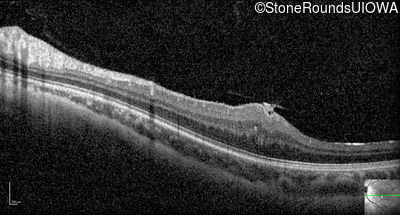

Optical Coherence Tomography - Right - 20/2000

Exemplar / OCT Stack